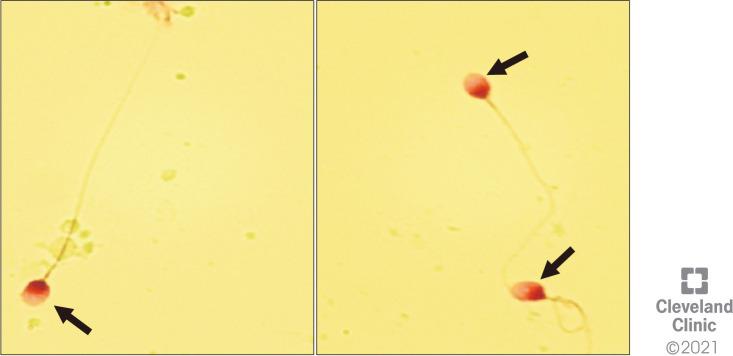

Azoospermia is defined as the absence of spermatozoa in the pellet of a centrifuged semen sample. In fact, when a basic semen analysis fails to detect sperm in the ejaculate, there is still the possibility of detecting rare sperm after centrifugation of the sample and examination of the pellet. In this study, we assessed the role of Cytospin centrifugation in combination with the nuclear fast picroindigocarmine (NF-PIC) staining in identifying sperm in azoospermic samples.

Semen samples of 251 men diagnosed as having azoospermia after standard examination were further analyzed by Cytospin centrifugation in combination with NF-PIC staining.

Sperm were detected in 60 men (23.9%), thus changing their diagnosis to cryptozoospermia.

By identifying sperm in the semen of men who were thought to have total azoospermia, the Cytospin NF-PIC test can alter the diagnosis and further treatment of these men.